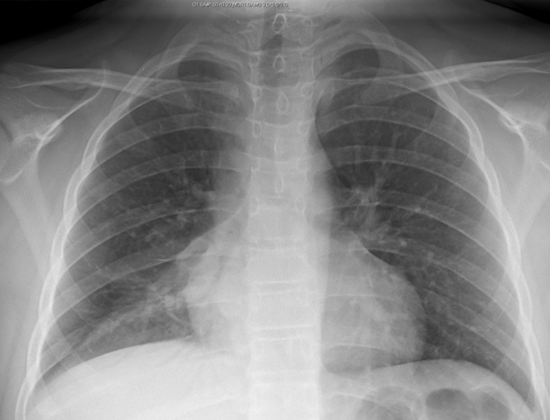

F – Fields

Lung fields should generally be uniformly dark grey.

Uniformly Dark Grey Lung Fields

Increased density may be due to airspace disease such as pneumonia, masses, pleural effusions, pulmonary edema, or atelectasis

Left Lower Lung with Effusion